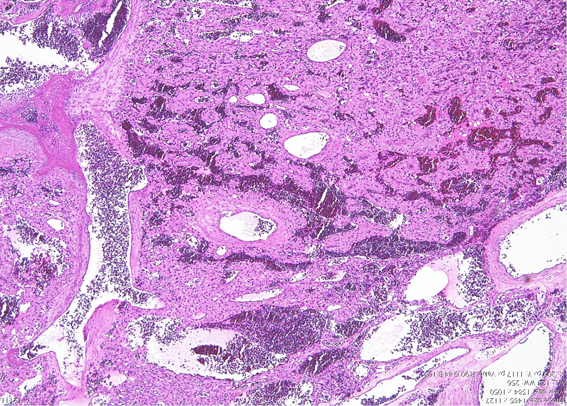

畑中佳奈子の病理教室:血管芽腫

小脳症状で発症した40代男性の症例

上記の症例の病理所見

弱拡では多数の血管が腫瘍の中に見られる,赤血球を含む大小の血管腔で構成される腫瘍である。

間質に増殖する淡桃色の胞体や空胞が豊かなstromal cells,この部分はcellular variantと呼ばれる。stromal cellでは,VEGF(血管内皮増殖因子)とVHL protein(フォンヒッペルリンドー病関連蛋白)が染まるので,この腫瘍細胞が激しい血管増殖を促していると考えられる。

毛細血管の増殖を主とするreticular variantと呼称される部分もある。大きな血管芽腫ではcellular variantとreticular variantが混在してあるのが通常である。